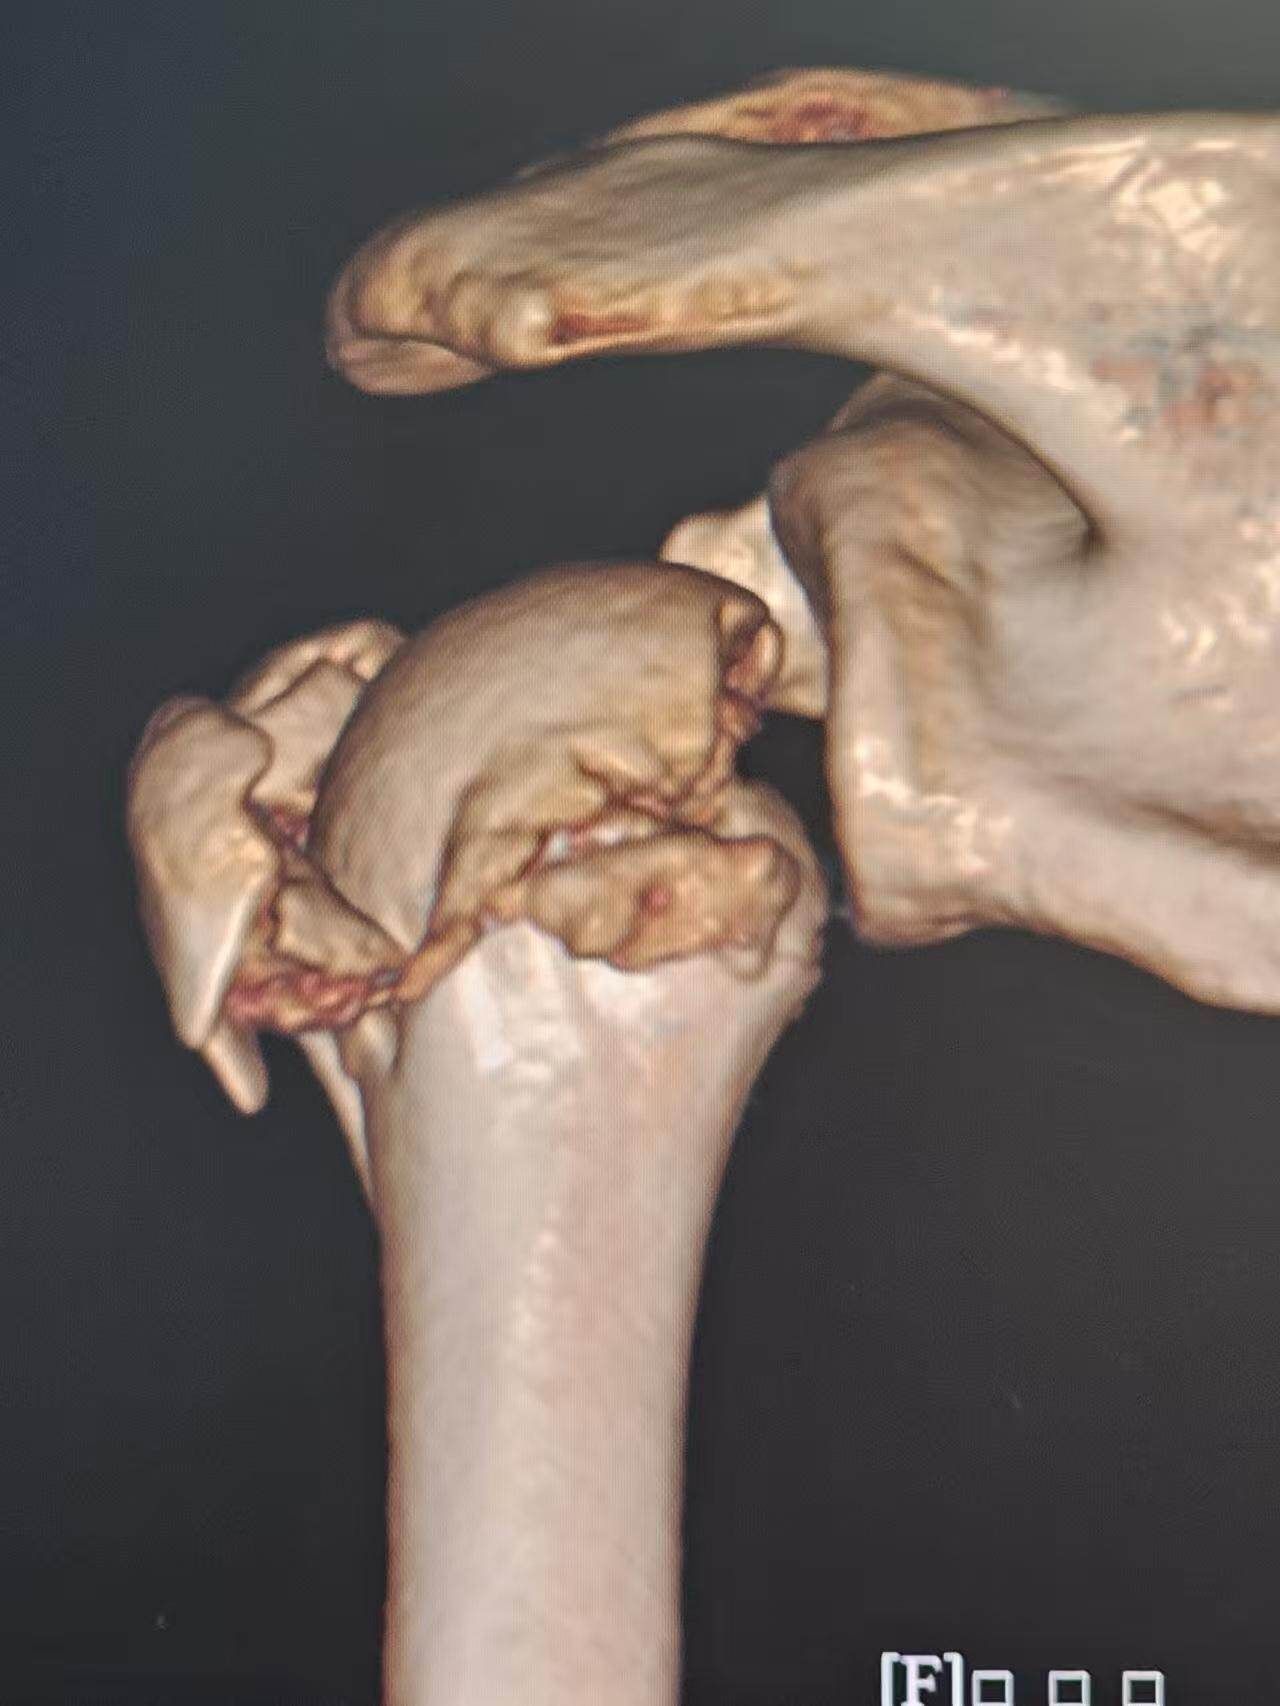

近日,广州的张先生(化姓)在骑电动车时不慎与小轿车碰撞,摔倒后肩膀着地,当即感到剧烈疼痛,活动受限,后诊断为“左侧肱骨近端骨折”,属于治疗难度较高的Neer 4部分骨折,心急如焚的他随即前往南方医科大学第三附属医院肩肘外科求医。

因此,王义隽团队特别制定了个性化方案——团队原创的“髓内骨距支撑钢板”固定技术。这项技术的核心创新在于,巧妙利用了骨折块之间已形成的“天然手术通道”,“传统方法多从外侧进行固定,往往难以重建肱骨内侧这一关键的‘力学核心’,而我们的思路是‘由内而外’——借助骨折本身形成的通道,将特制钢板植入骨髓腔内部,先在直视下精准复位并固定内侧骨距,再结合外侧钢板形成双重加固,构建一个内外协同的立体稳定系统。”术后,张先生疼痛明显减轻,数十天后便开始康复锻炼。